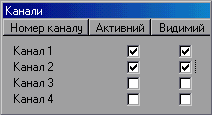

При знятті ПХ за

допомогою вбудованих функцій програми (про що свідчить вимкнений прапорець

"Використовувати зовнішній пакет" у вікні настроювань ![]() ) необхідно вказати

необхідні активні і видимі канали у вікні каналів

Рисунок 8.3 – Карта розташування хребців з вибраним елементом

Рисунок 8.4 – Вікно каналів

Регулюючи силу притиснення датчиків у міжхребетних западинах і вибираючи коефіцієнт підсилення датчиків (для зовнішнього знімного пристрою це регулятор на передній панелі), досягнути появи стійких ПХ із максимальним рівнем амплітуди сигналу в двох каналах [19].